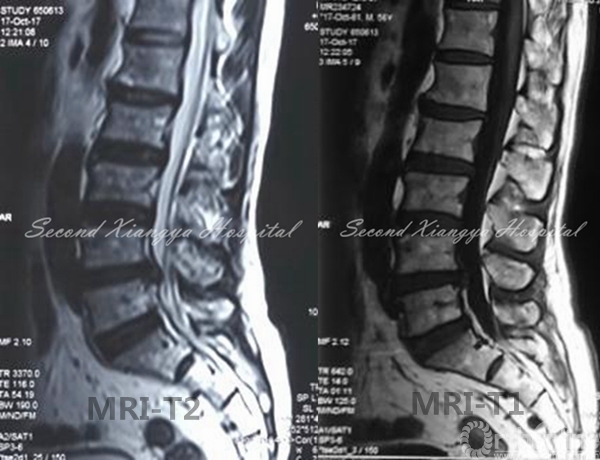

6.辅以头灯放大镜,或者显微镜,直视下用刮匙、髓核钳等器械可有效摘除突出髓核(非游离型)。先以刀片切除前外侧纤维环,以Cobb剥离器沿终板剥离椎间盘,髓核钳夹出,直至椎体后缘。以椎体间撑开器撑开椎间隙,用刮匙去除附着在椎体后缘的纤维环,可见纤维环右侧有破口,以神经剥离子勾出脱出的髓核,枪式椎板咬骨钳修正后缘增厚的纤维环后进一步探查椎管内有无残留髓核组织,但注意不要过度在椎管内操作防止出血。减压完成后,可见反光的硬膜囊前部。

显微镜操作

镜下图片

显微镜下髓核摘除视频